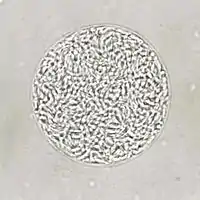

| Giemsa stained T. gondii tachyzoites, 1000× magnification | |